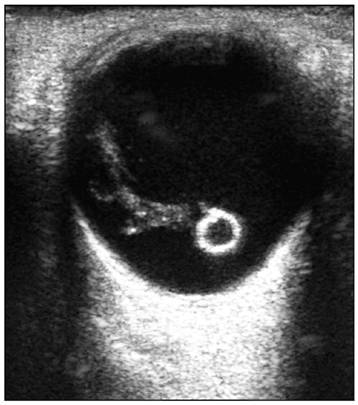

Рис. 9. Эхограмма глазного яблока. Инородное

тело глазного яблока (искусственный хрусталик)